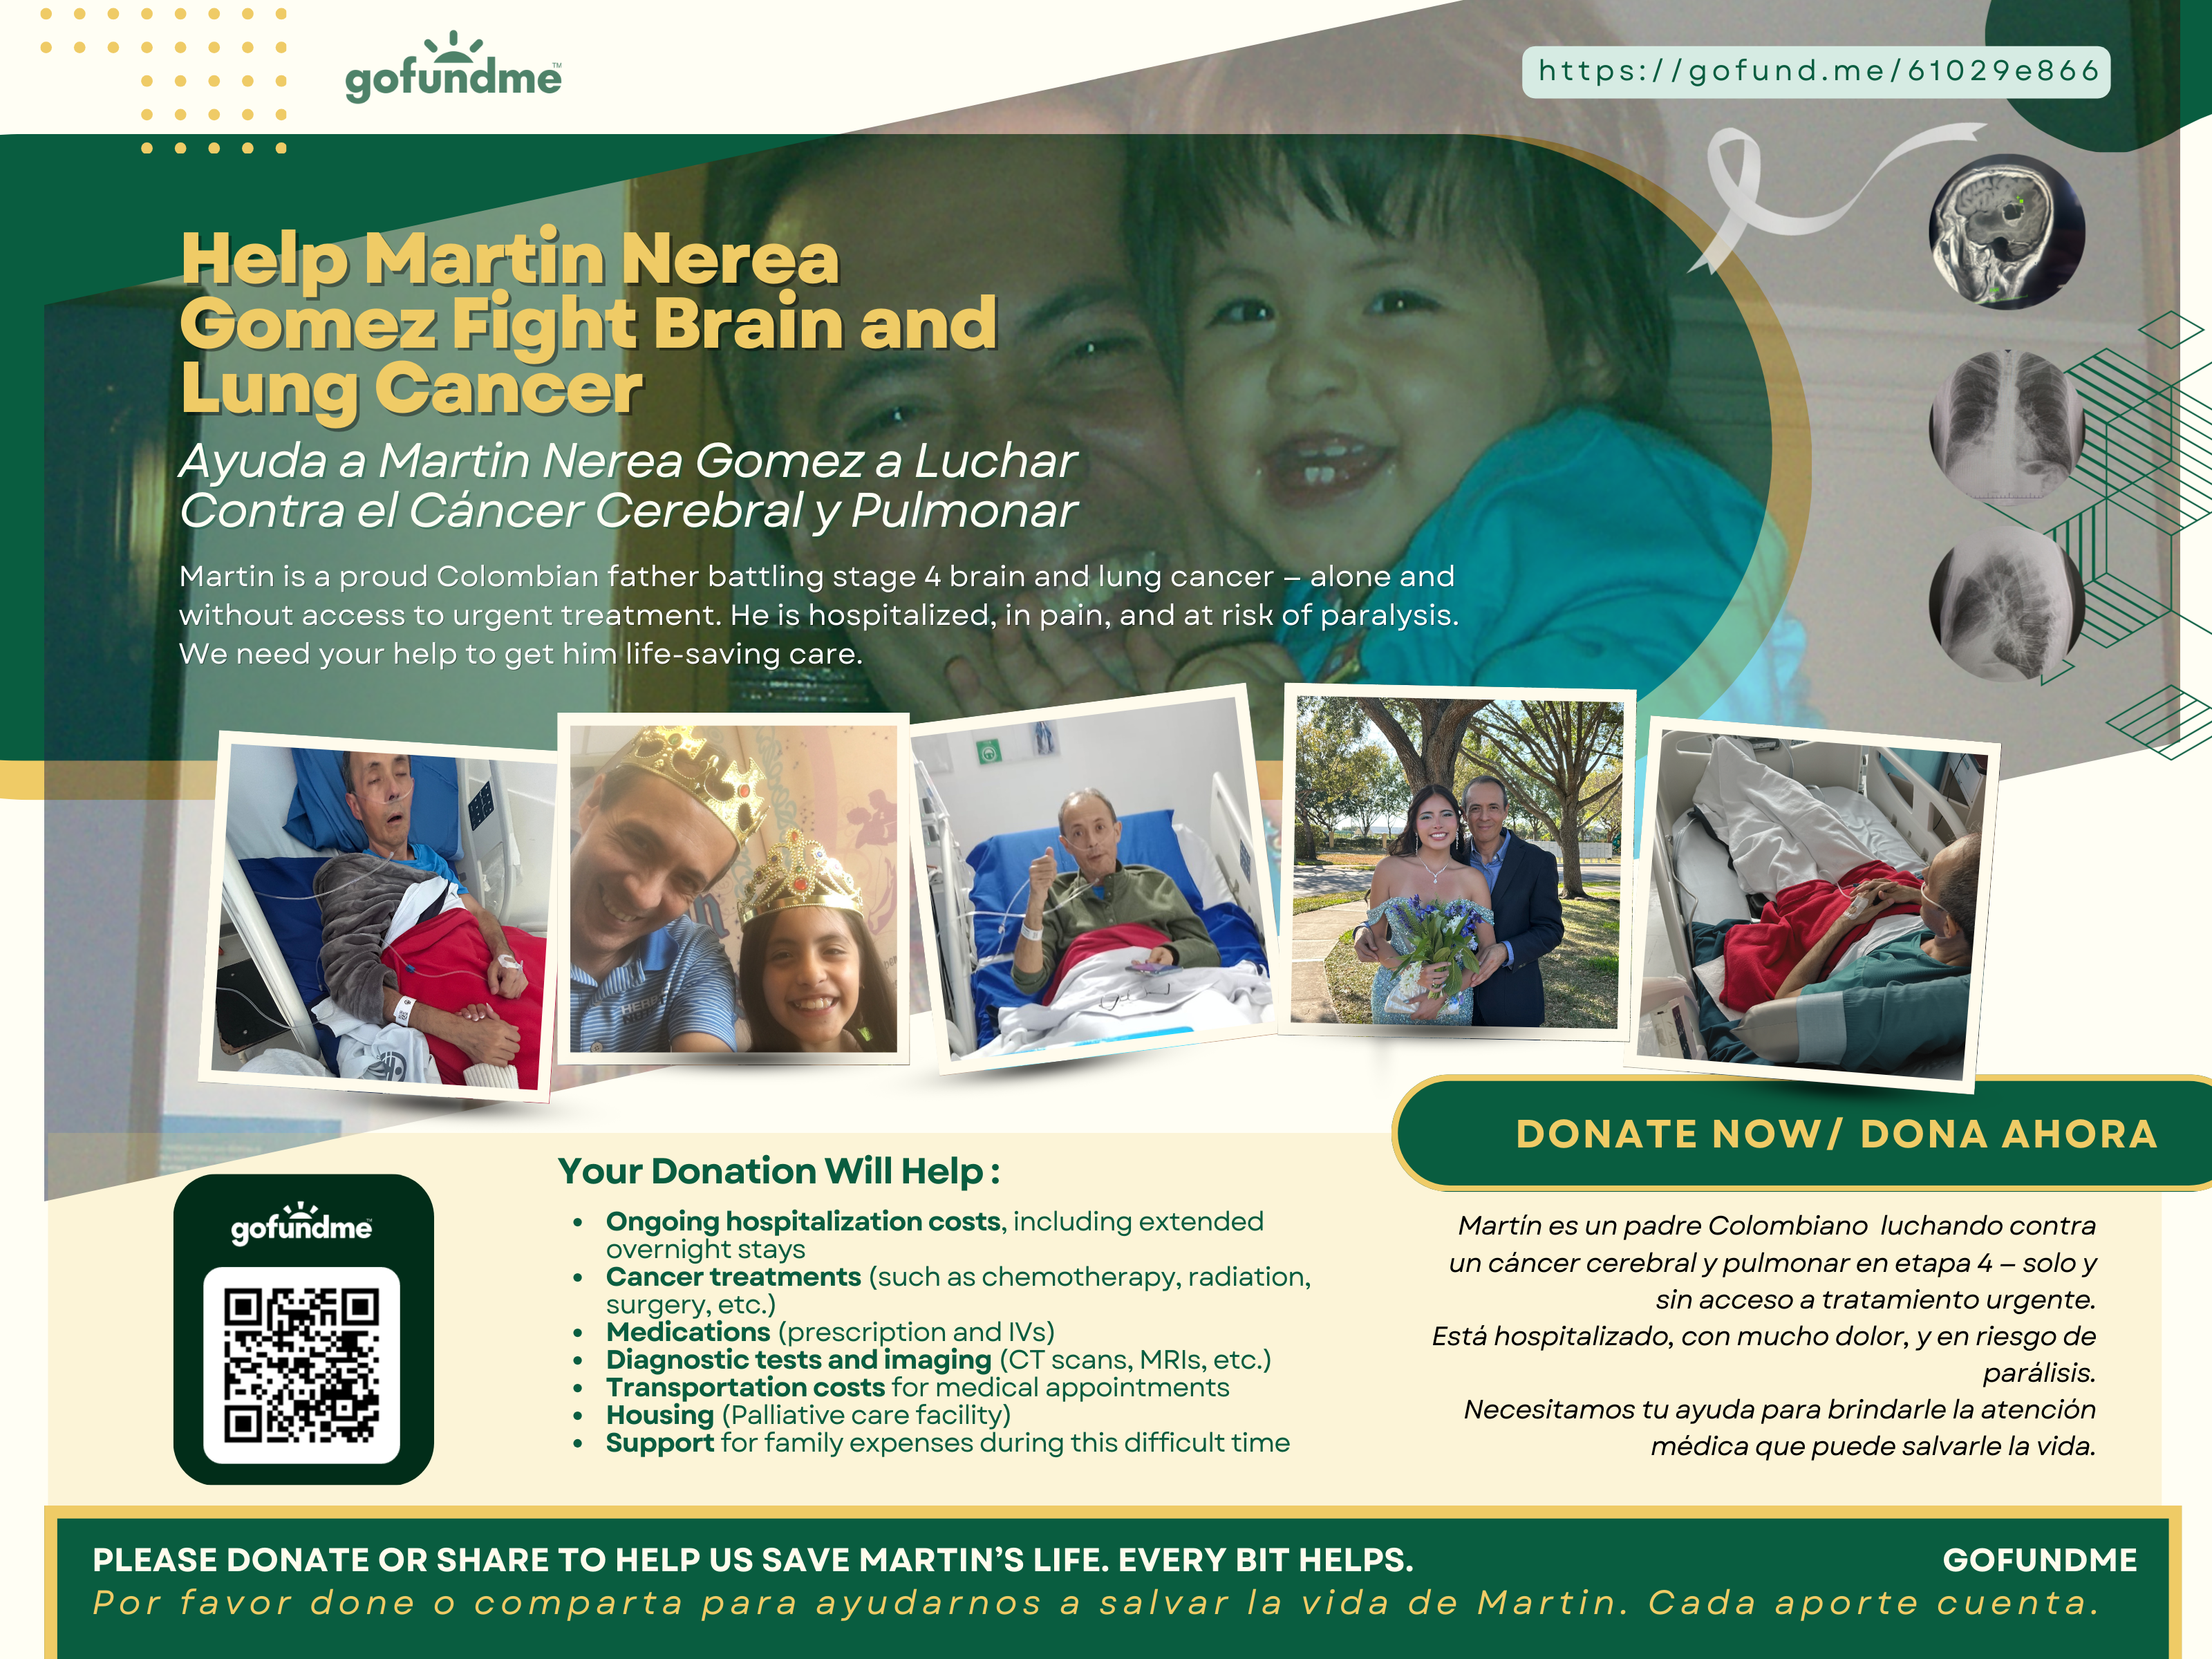

My name is Maria Alejandra Nerea and I am organizing this fundraiser for my dad, Martin Nerea Gomez. He was and currently still is battling stage 4 brain cancer and lung cancer.

He is fighting as hard as he can against this disease that has already taken so much from us. He is in so much pain not just physically, but emotionally.

My dad is the most kindhearted, loving dad i could've ever asked for. As you can see his smile always light up every room. He taught me everything i know about love, empathy, resilience and kindness.

His current condition:

My dad had beat lung cancer in 2022 after undergoing an extremely risky and expensive surgery. Over 20% of his lung was removed, leaving him with lifelong, chronic pain.

In December of 2024, what started as a small cough became our worst nightmare. With limited access to health care, we paid what exams we could out of pocket. Scans confirmed a tumor, this time on his bronchus, where air flows. This tumor was slowly suffocating my dad. He would have coughing episodes so bad he could barely breathe.

My dad had to leave the country in May and 3 months later he has yet to start any treatment. Due to Colombia's healthcare system, that means months of waiting for each test with insurance. While he waited, the cancer spread to his kidney. Now to his brain. Two tumors are causing him to loose feeling from the left side of his face, his mouth, and his eye. He is at risk for paralysis.

He has been hospitalized multiple times, coughing blood, in excruciating pain, all while being thousands of miles away from us. Right now my dad urgently needs radiation, chemotherapy, medications, and housing close to the hospital so he can get treatment safely.